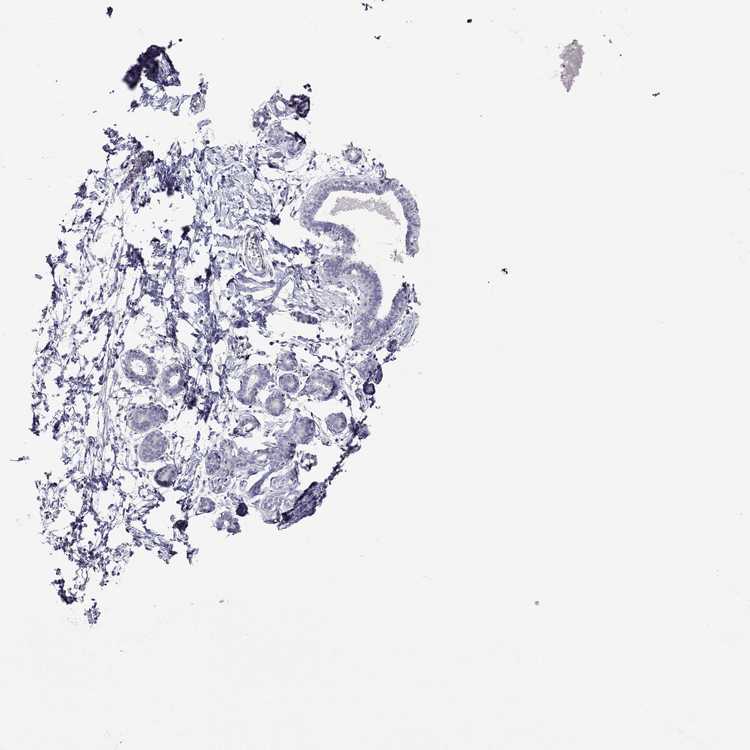

TISSUE PRIMARY DATA BREAST Show tissue menu

Breast

BREAST - Antibody stainingi

Antibody staining in the annotated cell types in the current human tissue is reported as not detected, low, medium, or high, based on conventional immunohistochemistry profiling in selected tissues. This score is based on the combination of the staining intensity and fraction of stained cells.

Each image is clickable and will lead to virtual microscopy that enables deeper exploration of all samples and also displays staining intensity scores, fraction scores and subcellular localization as well as patient and tissue information for each sample.

Antibody HPA074762Antibody CAB075684

Adipocytes Not detectedNot detected

Glandular cells Not detectedNot detected

Myoepithelial cells Not detectedNot detected